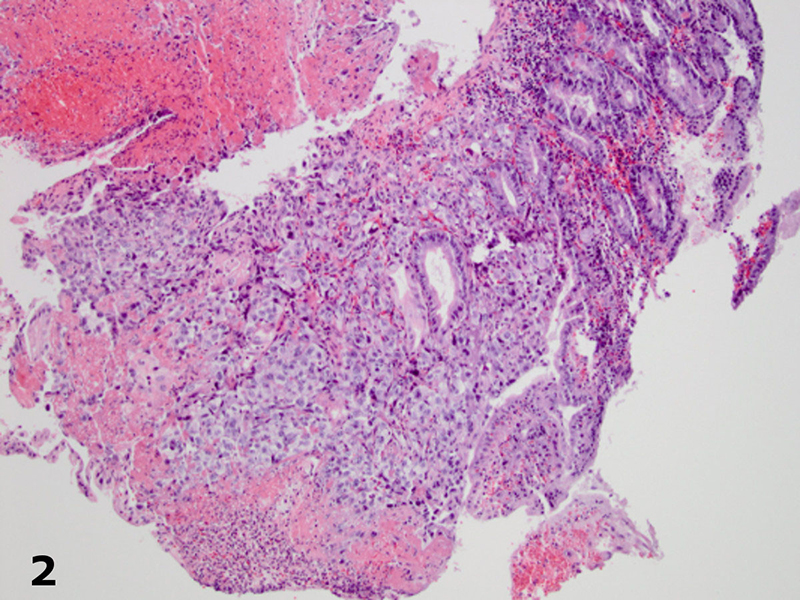

Imaging studies (computed tomography scan of the abdomen and chest radiograph) did not reveal a source for the bleeding or a mass lesion. The EGD demonstrated multiple red-brown polypoid masses within the stomach and duodenum (Figure 1).The biopsies, of both the stomach and duodenum, demonstrated large cells with amphophilic cytoplasm and irregular nuclei with vesicular chromatin and prominent nucleoli infiltrating the lamina propria (Figures 2 and 3). There was subtle vasoformation and, notably, no overlying dysplasia was identified. The neoplastic cells were positive for pan-cytokeratin, cytokeratin 7 (Figure 4), CD31 (Figure 5), and CD34. The neoplastic cells were negative for CDX2, TTF-1, S-100 protein, cytokeratin 20, cytokeratin 5/6, and calretinin.